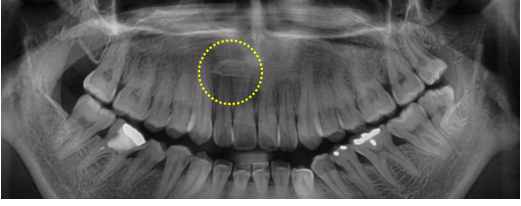

교정 상담 중 촬영한 엑스레이에서 소구치 뿌리 바로 위에 매복 과잉치가 발견된 사례입니다.

정상 치아이동을 위해 발치가 필요한 상태였습니다.